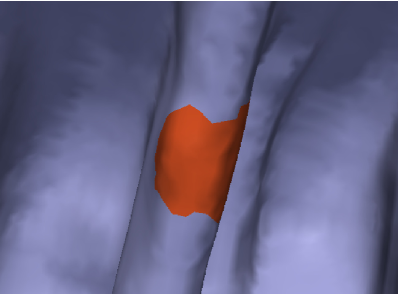

Figure 7 shows the result after a few iterations; comparing to Figure 5, it can be readily seen that this motion achieves a better trade-off in terms of noise reduction and polyp preservation. Figure 8 evidences the difference with a comparative image: the result of the motions by and are shown in gray and in orange, respectively. On the polyp protrusion, the orange surface is above the gray surface, while the opposite is observed in the surrounding area. This shows that the evolution by leads to better polyp enhancement.

Given a candidate patch , a ring around is computed, in order to consider geometrical measurements with respect to the area surrounding the patch. The ring is calculated by dilating the patch a certain geodesic distance, such that the areas of and are equal. The geodesic distance computation is performed using the algorithm by [50]. Figure 14 shows a candidate patch (actually a true polyp), and its corresponding ring.